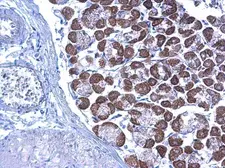

Images

Description

Applications